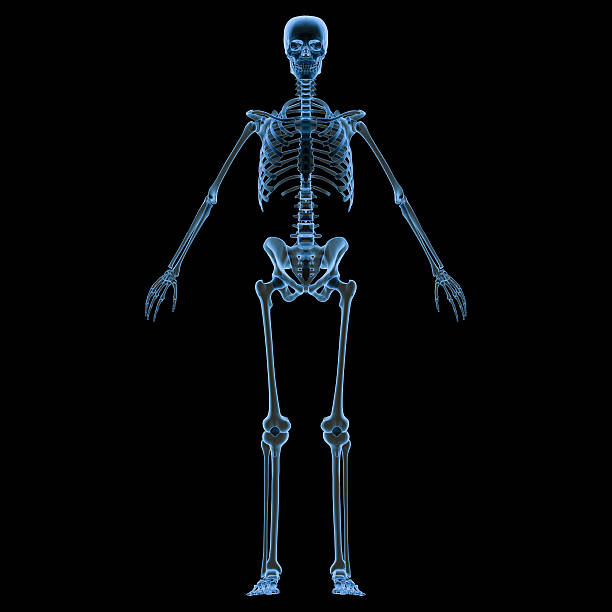

ये है मानव शरीर की सबसे लंबी और सबसे छोटी हड्डियां, जानें इसके बारे में

नई दिल्ली। (Longest and Smallest Bone of Human Body) आपके शरीर में कुल 206 हड्डियां होती हैं। इसकी संरचना अलग-अलग ढंग की होती है। हड्डियों के कारण ही मनुष्य का शरीर खड़ा हो पाता है। हड्डियों का भार हमारे शरीर के वजन का 14 प्रतिशत होता है। ये 50 प्रतिशत पानी और 50 प्रतिशत ठोस पदार्थ से मिलकर बनती हैं। यह ठोस पदार्थ हमारे मसल्स के एक्टिव टिशूज होते हैं, जिनसे हड्डियों का विकास होता रहता है। ज्यादातर हड्डियां बीच से खोखली होती हैं। इनके बीच एक जैली होती है, जिसे बोनमैरो कहते हैं। इस जैली में ब्लड सेल्स बनते हैं। रेड ब्लड सेल्स शरीर के सभी अंगों में ऑक्सीजन पहुंचाते हैं और सफेद ब्लड सेल्स तुम्हारी रोग प्रतिरोधक क्षमता बढ़ाते हैं। 206 हड्डियों में शरीर की सबसे बड़ी हड्डी हमारी जांघो में होती है जिसे फीमर कहते हैं और शरीर की सबसे छोटी हड्डी हमारे कान की होती है जिसे स्टेपीज के नाम से जाना जाता है। आइए इससे जुड़ी और बाते जानते हैं।

फीमर मानव शरीर में पाई जाने वाली सबसे लंबी हड्डी है। यह लगभग 19.9 इंच लंबा होता है और आमतौर पर इसे जांघ की हड्डी के रूप में जाना जाता है। केवल उसकी जांघ को देखकर यह अनुमान लगाया जा सकता है कि फीमर सबसे लंबी हड्डी है। यह कूल्हे से नीचे घुटने के क्षेत्र तक फैला होता है।

स्टेपीज मानव शरीर की सबसे छोटी और हल्की हड्डी होती है। इसकी लंबाई लगभग 11 इंच (28 से.मी.) होती है। यह हमारे कानों के बीच में मौजूद होते हैं। मध्यम कान में तीन हड्डियां हैं जो मानव शरीर में सबसे छोटी हड्डियों में से एक हैं।